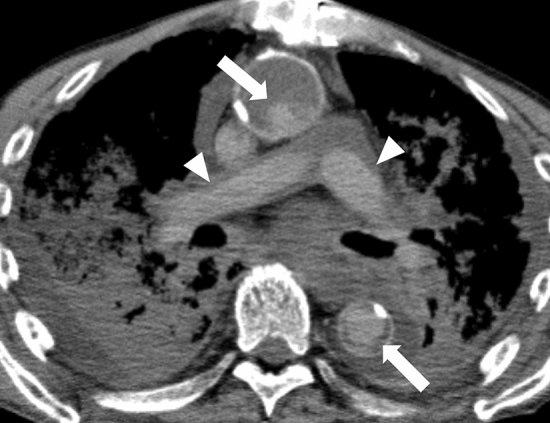

Livor mortis, also known as postmortem hypostasis, is a postmortem change that occurs as a result of circulatory arrest, which leads to a deprivation of blood supply. On CT images, this can manifest as hyper-attenuation in the dorsal venous sinuses, such as the superior sagittal and transverse venous sinuses (Fig. 1a and 1b) [18], and in the lumens of the heart and aorta, especially in the thoracic aorta (sometimes also in the inferior vena cava). This is due to the concentration of the hemoglobin molecule in sedimented erythrocytes and can sometimes lead to the formation of a fluid–fluid level (Fig. 1c) [19]. In the lungs, increased attenuation can be seen on the gravity side, resembling ground glass opacity with horizontal plane formation (Fig. 1d) [20], and this finding becomes more conspicuous over time [21]. Additionally, a distinct blood deposition with a horizontal plane in the lumens of the heart and aorta can indicate a hyper-fibrinolytic system due to acute death. In contrast, a cast-like hyperattenuating area can be seen in the pulmonary artery and aorta during the long death phase and in the agonal stage of chronic disease (Fig. 2) [22]. Subcutaneous edema and skin thickening can also occur and are generally symmetrical [23].

Fig. 1.

Representative CT images of early regular postmortem changes. a, b increased density in the superior sagittal sinus (arrowheads), brain edema (dorsally dominant), and loss of the differentiation between the gray and white matter. c thickened left ventricular wall (white arrowheads), hyperattenuating in the gravity side (black arrowhead), and dilatation in the right heart cavities (arrows). d fluid in the bilateral main bronchus (arrows) and the increased attenuation, such as ground-glass opacities with the horizontal plane formation on the gravity-dependent side of the lungs (arrowheads). e narrowed short diameter of the aorta and the hyperattenuating and thickened aortic wall (arrow). f intrahepatic portal venous gas (8 h elapsed from death without cardiopulmonary resuscitation). g obscuring of outline and swelling in the pancreas (arrowheads)

Rigor mortis is a postmortem change that occurs as a result of muscle stiffness caused by chemical changes in the muscles after death. On CT images, this can manifest as an increase in the heart's ventricular wall thickness compared with antemortem images (Fig. 1c) [24], narrowing of short arterial diameters, and hyper-attenuation and thickening of the arterial wall, reflecting smooth muscle contraction. These findings are most prominent in large arteries, such as the aorta and pulmonary artery (Fig. 1e) [25–27]. Skeletal muscle, which is striated muscle, also exhibits increased attenuation on postmortem CT than on antemortem CT [28].

Changes secondary to the cessation of circulation

After circulatory arrest, the vasculature is at a mean circulatory filling pressure, which is hydrostatic pressure (approximately 7 mmHg). This pressure is slightly higher than the antemortem right heart system diastolic pressure, which leads to a shift of blood volume to the right heart system after death and can result in dilatation of the right heart system and superior vena cava (Fig. 1c) [29] and narrowing of the aorta (Fig. 1e) [30, 31].

Additionally, there are other characteristic postmortem CT findings of brain parenchyma associated with cessation of circulation, such as edematous changes that increase the water content of the gray matter and obscure the distinction between gray and white matter (Fig. 1a) [32], narrowing of sulci and ventricles, and brain swelling when vasogenic edema is prominent (Fig. 1a) [33].

Loss of air in the trachea can also occur as fluid exudates from the lung interstitium into the alveoli and airways (Fig. 1d). This is a common finding when pleural effusion, lung consolidation, and atelectasis are present. Membrane hyperpermeability is thought to be one of the mechanisms [34].